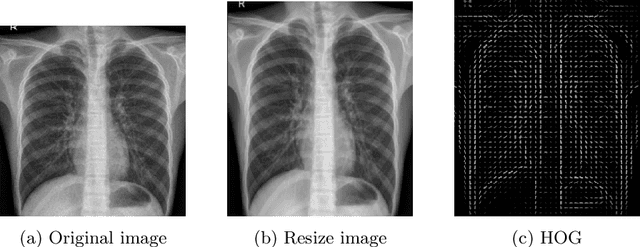

Detecting and classifying diseases using X-Ray images is one of the more challenging core tasks in the medical and research world. Innovations and revolutions of Computer Vision with Deep learning methods offer great promise for fast and accurate diagnosis of screening and detection from chest X-Ray images (CXR). This work presents rapid detection of diseases in the lung using the efficient Deep learning pre-trained RepVGG algorithm for deep feature extraction and classification. We performed automatic classification of X-Ray images into three categories as Covid-19, Pneumonia, and Normal X-Ray cases. For evaluation, first, we used a histogram-oriented gradient (HOG) to detect the shape of the region of interest (ROI). We used the ROI object to improve the detection accuracy for lung extraction, followed by data pre-processing and augmentation. Then a pre-trained RepVGG model is used for deep feature extraction and classification, similar to VGG and ResNet convolutional neural network for the training-time and inference-time architecture transformed from the multi to the flat mode by a structural re-parameterization technique. Next, using the Computer Vision technique, we created a feature map and superimposed it on the original images. We used this technique for the automatic highlighted detection of affected areas of people's lungs. Based on the X-Ray images, we developed an algorithm that classifies X-Ray images with height accuracy and power faster thanks to the architecture transformation of the model. We compare deep learning frameworks' accuracy and detection of disease. The study shows the high power of deep learning methods for X-Ray images based on COVID-19 detection utilizing chest X-Ray. The proposed framework shows better diagnostic accuracy by comparing popular deep learning models, i.e., VGG, ResNet50, inceptionV3, DenseNet, and InceptionResnetV2.